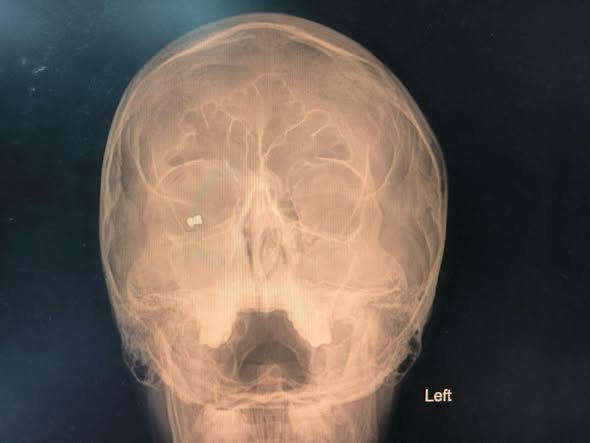

При извършения спешен офталмологичен преглед е установено метално чуждо тяло в орбитата на дясното око, както и разкъсна рана на клепача, съответстваща на входно отвърстие от прострелване. Зрението на пациента към момента на приемане е било силно намалено – до броене на пръсти пред окото.

След пълни изследвания и подготовка, екипът на доц. Яни Здравков извършва спешна операция, при която успешно е отстранено метално чуждо тяло – съчма от въздушна (газова) пушка.